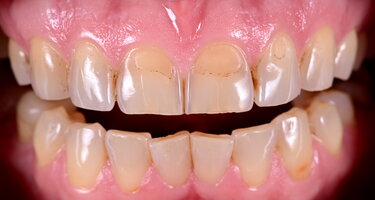

In this case, the patient expressed a strong preference for a relatively high translucency with natural incisal characterizations (Figs. 9-10).

Figures 9-10: IPS e.max lithium-disilicate crowns and vaneers and an IPS e.max Prime zirconia bridge